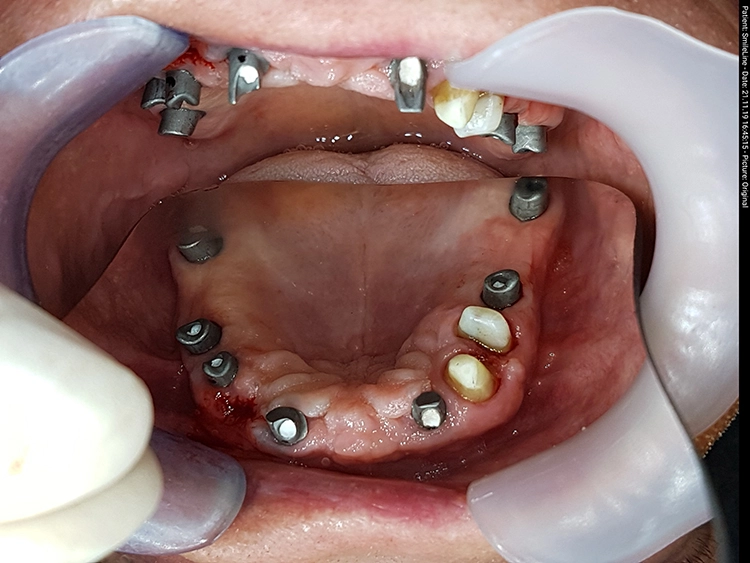

Nach einer – aufgrund eines Campingurlaubs von sechs auf acht Monaten – verlängerten Heilphase konnte der Patient implantiert werden. In der Röntgenkontrollaufnahme zeigten sich stabile knöcherne Strukturen in den augmentierten Bereichen des Sinus. Die Insertionen erfolgte gemäß Protokoll frei Hand auf Grundlage der DVT-Aufnahme und orientiert an der alten Teleskopprothese.

Die Freilegung der Implantate erfolgte mit minimalinvasiver Stichinzision. Die Verschlussschrauben wurden entfernt und Gingivaformer eingesetzt, um das Weichgewebe auszuformen. Die ursprüngliche Teleskopprothese wurde im Bereich der Gingivaformer ausgeschliffen und mit einer Gaumenplatte erweitert.

So konnte sie als Interimsversorgung, verankert auf den Zähnen 23 und 24, über den Gingivaformern als Interimsersatz genutzt werden und sich das Weichgewebe unbelastet um die Implantate herum ausformen. Einige Wochen später – wiederum verzögert durch einen Campingaufenthalt – konnte auf dem mittlerweile befestigten und stabilen Weichgewebe für die Herstellung der definitiven Restaurationen abgeformt werden. Hier ist von Vorteil, dass die Conelog Abformpfosten nicht in den Konus des Implantats eingreifen, sondern auf der Implantatschulter aufliegen, wodurch ein Höhenversatz bei der Abformung vermieden wird.